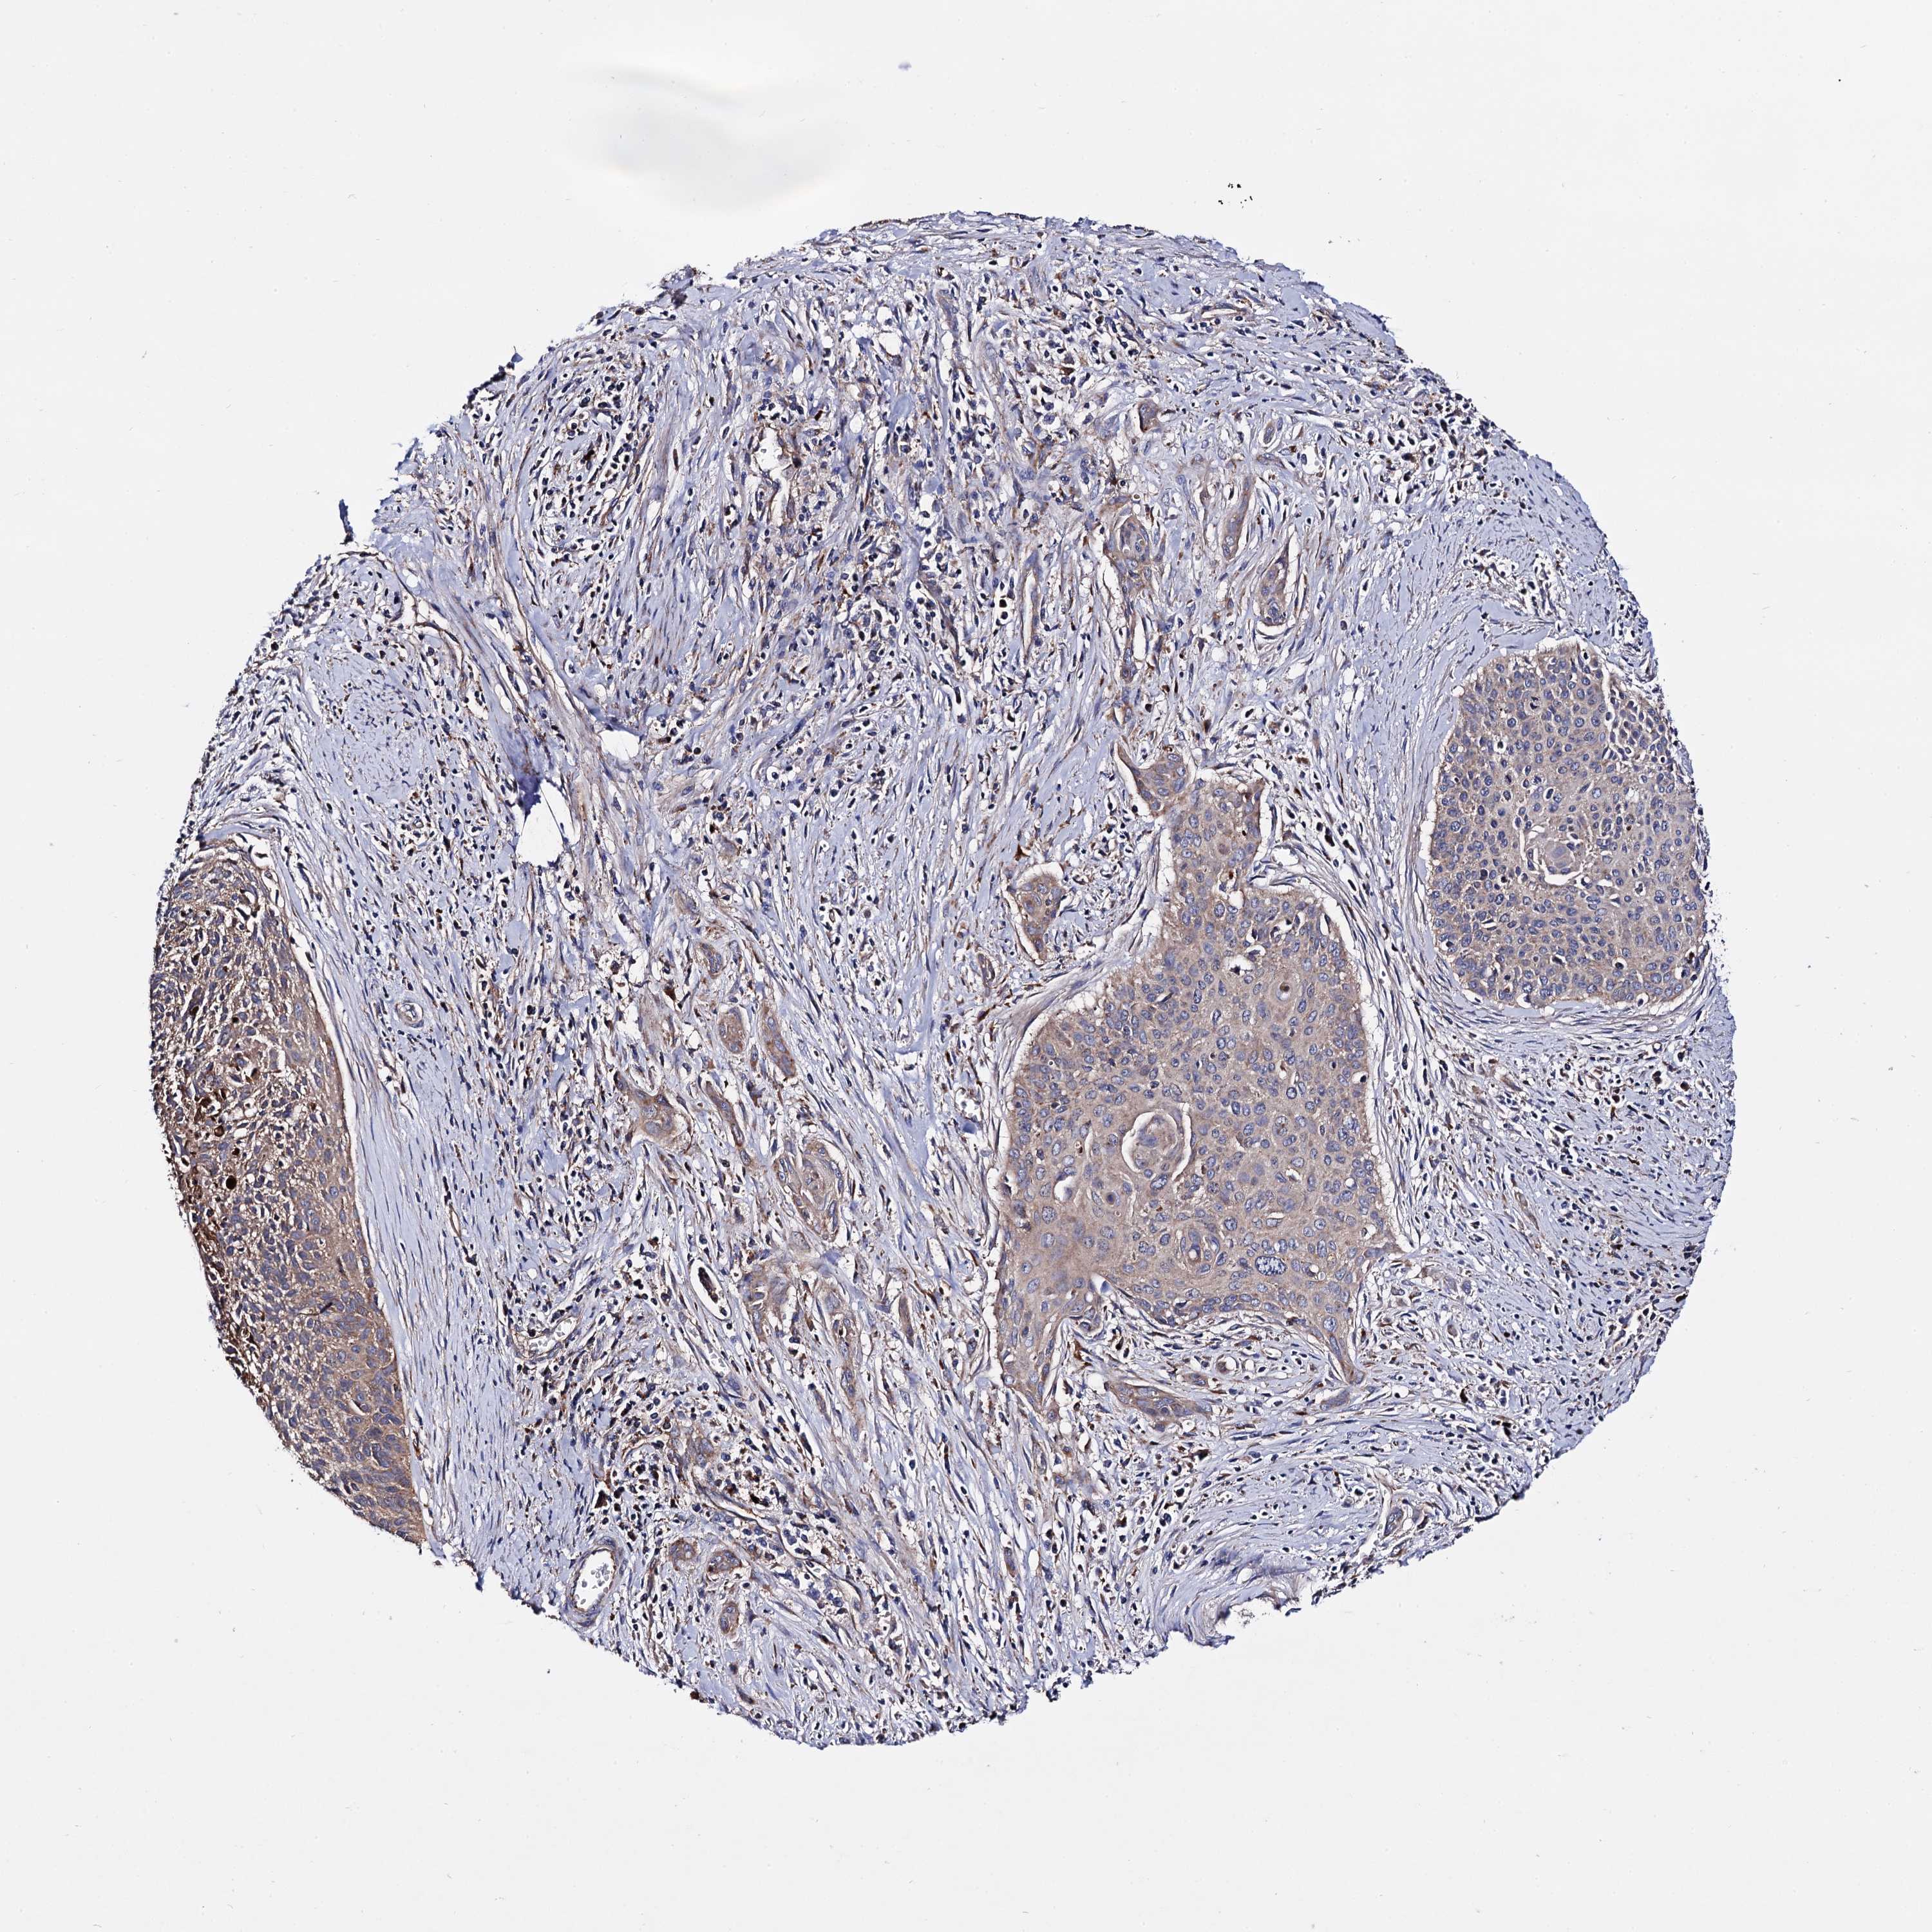

CERVICAL CANCER - Protein expressioni

A mouse-over function shows sample information and annotation data. Click on an image to view it in a full screen mode. Samples can be filtered based on level of antibody staining by selecting one or several of the following categories: high, medium, low and not detected. The assay and annotation is described here.

Note that samples used for immunohistochemistry by the Human Protein Atlas do not correspond to samples in the TCGA dataset.

Antibody stainingi

Antibody staining in the annotated cell types in the current human tissue is reported as not detected, low, medium, or high, based on conventional immunohistochemistry profiling in selected tissues. This score is based on the combination of the staining intensity and fraction of stained cells.

Each image is clickable and will lead to virtual microscopy that enables deeper exploration of all samples and also displays staining intensity scores, fraction scores and subcellular localization as well as patient and tissue information for each sample.

Antibody HPA040845

Staining

High

Medium

Low

Not detected

Intensity

Strong

Moderate

Weak

Negative

Quantity

>75%

75%-25%

<25%

None

Location

Nuclear

Cytoplasmic/membranous

Cytoplasmic/membranous,nuclear

Squamous cell carcinoma, NOS

Adenocarcinoma, NOS